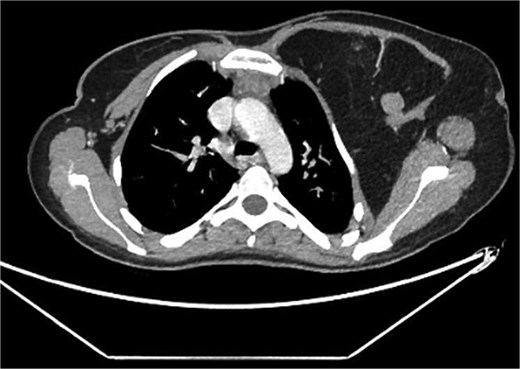

A 22-year-old female presented with progressive swelling in the left anterior chest wall above the left breast, associated with needle-like chest pain, left upper limb tingling, and weakness. The patient had a history of childhood cystic hygroma in the left axilla, previously excised. She denied constitutional symptoms but reported compressive symptoms such as shortness of breath, dysphagia, and hoarseness. A family history of breast cancer with thyroid metastasis was noted in her mother. On examination, the patient exhibited multiple bilateral solitary thyroid nodules and a bulky swelling in the left anterior chest and axilla. Computed tomography (CT) imaging (Fig. 1) revealed hypodense bilateral thyroid nodules, with magnetic resonance imaging (MRI) (Fig. 2) showing an enhancing left axillary lesion (2 cm, previously 1 cm) and an anterior chest wall lesion (1 cm). The mass, measuring 23 × 8 cm, extended to the lower left neck, left chest wall, and left axilla, encasing the neurovascular bundle without muscle or osseous invasion (Fig. 3). Fine-needle aspiration (FNA) cytology (Fig. 4) of the right thyroid nodule indicated atypia of undetermined significance (Bethesda III), while left-sided nodules and biopsies from the axilla, breast, and neck confirmed benign mature adipose tissue. The patient underwent total thyroidectomy, level V left neck exploration, and excision of lipomatous masses from the axilla, anterior chest, and breast, involving multiple surgical teams. Intraoperatively, vocal cords were preserved, and clear planes for lipoma excision were identified. The total excised lipomatous tissue weighed 13.57 kg (Fig. 5). Pathological examination confirmed mature adipose proliferation with no malignancy. Fluorescence in situ hybridization (FISH) ruled out MDM2 amplification, and genetic testing returned negative. Postoperatively, the patient developed deep vein thrombosis (DVT) in the left upper limb, diagnosed via Doppler study, and was treated with low-molecular-weight heparin (LMWH) followed by rivaroxaban. Follow-up MRI at 2 days and 3 months confirmed no residual or recurrent tissue growth. The patient started levothyroxine for thyroid function management and monitored for optimal dosing.

Interval increase in size of the large left upper lateral cervical, sub-pectoral, and axillary region fatty lesion protruding beyond the pectoralis major muscle into the upper breast region, keeping with lipomatosis.

Partially scanned left thoracic lipomatosis extending to the lower neck with mild mass effect over the left internal jugular vein. A multilocular goiter with a complex thyroid nodule is noted in the lower neck.